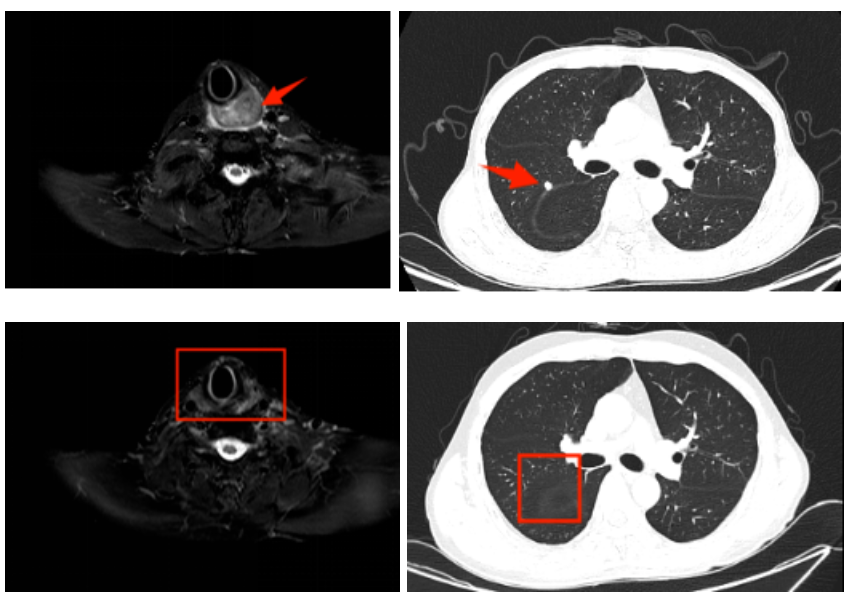

2023年8月,张先生因“发现左颌下肿物3个月”到我院鼻咽癌诊治中心就医,完善病理、影像学检查后明确为晚期下咽癌。由于肿瘤已侵犯甲状腺、食管等邻近器官,伴颈部淋巴结转移,不适合手术。随后,张先生参与了晚期头颈部肿瘤同期放化疗靶向增敏临床试验。经35次精准放疗及同步化疗,肿瘤和转移淋巴结明显缩小。

之后病情出现了进展,2023年12月复查时发现肺部有新发小结节,考虑远处转移。医疗团队迅速调整方案,先采用免疫联合靶向治疗,随后又定制了“口服化疗+靶向+免疫”的维持方案。